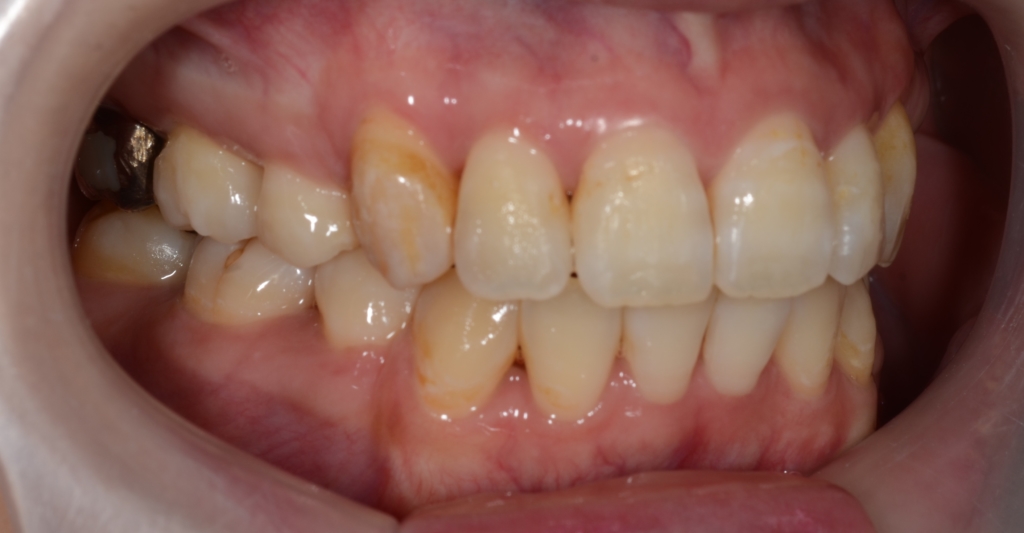

患者さんは、30代の女性(社会人)です。

「八重歯などのガタガタを治してきれいな歯並びになりたい!」

というのが一番の希望でした。

合わせて、口元が少しでも引っ込んで、お口を閉じる時にオトガイ辺りの「力」が抜けてしわが無くなればもっと嬉しい!とのことでした。

【Before】

#1.顎と歯の不調和による叢生(重度)

#2.上顎前突(出っ歯)傾向

と診断しました。